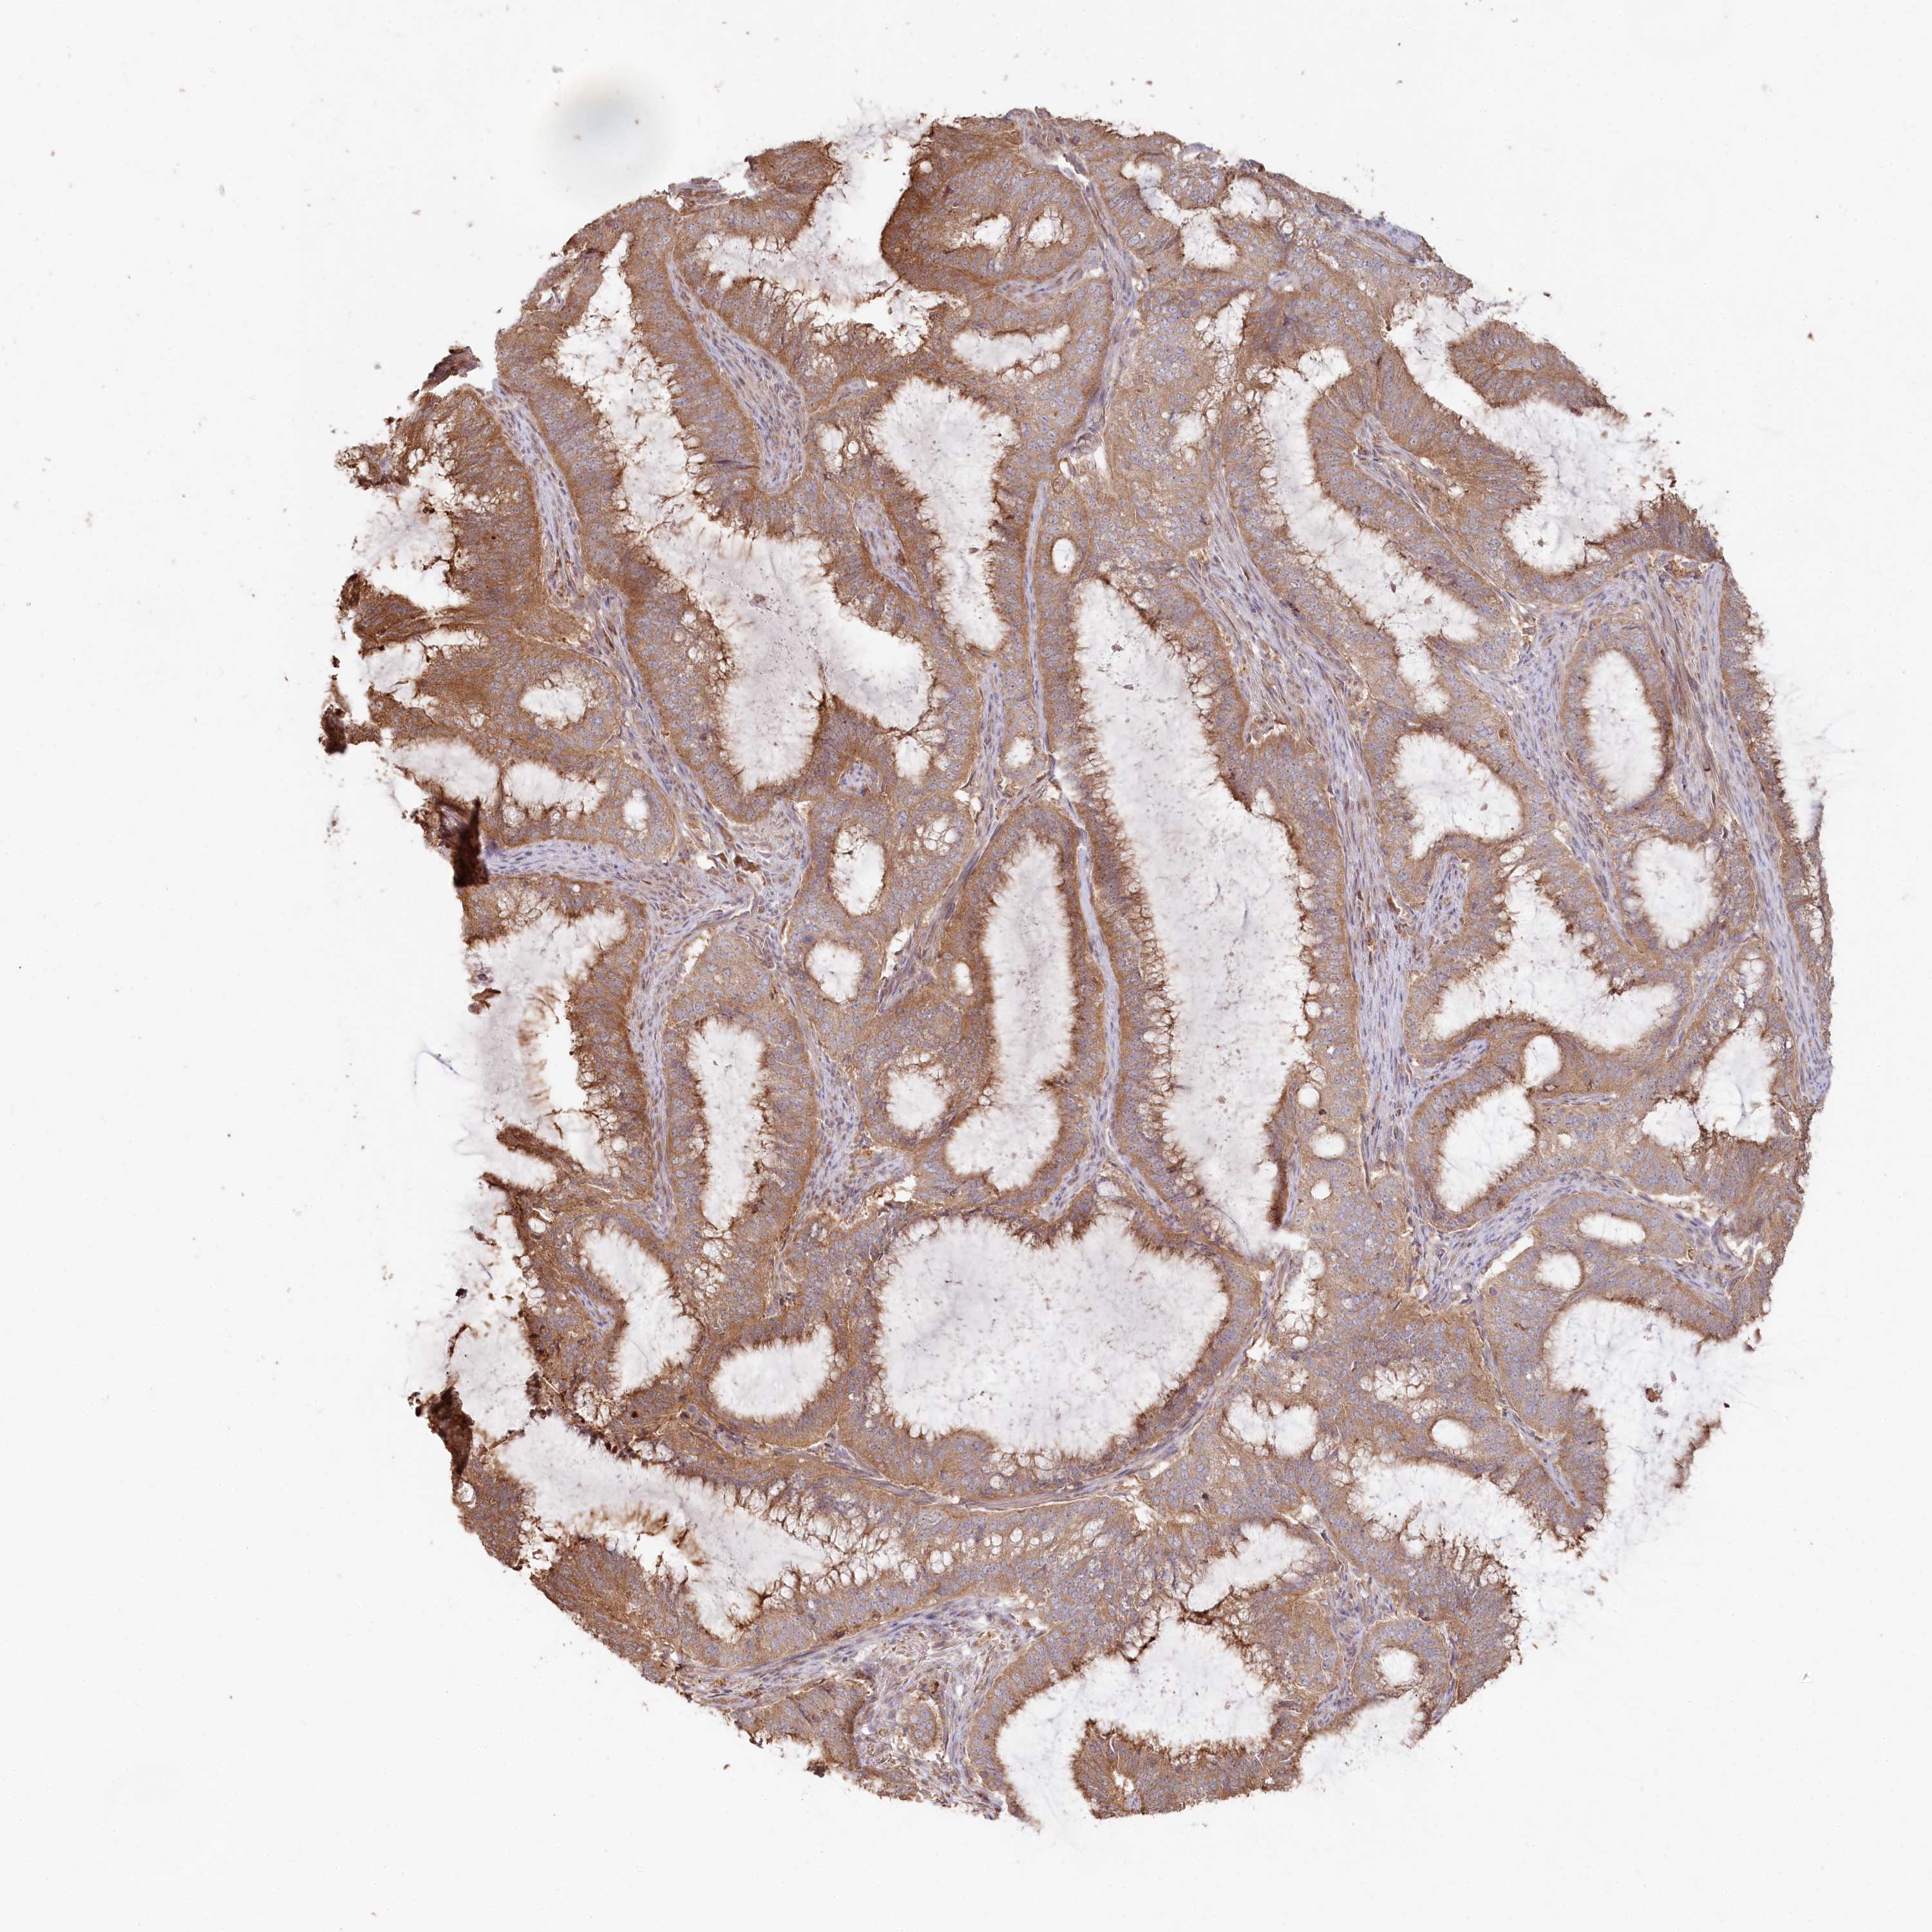

ENDOMETRIAL CANCER - Protein expressioni

A mouse-over function shows sample information and annotation data. Click on an image to view it in a full screen mode. Samples can be filtered based on level of antibody staining by selecting one or several of the following categories: high, medium, low and not detected. The assay and annotation is described here.

Note that samples used for immunohistochemistry by the Human Protein Atlas do not correspond to samples in the TCGA dataset.

Antibody stainingi

Antibody staining in the annotated cell types in the current human tissue is reported as not detected, low, medium, or high, based on conventional immunohistochemistry profiling in selected tissues. This score is based on the combination of the staining intensity and fraction of stained cells.

Each image is clickable and will lead to virtual microscopy that enables deeper exploration of all samples and also displays staining intensity scores, fraction scores and subcellular localization as well as patient and tissue information for each sample.

Antibody HPA038547

Antibody HPA038548

Staining

High

Medium

Low

Not detected

Intensity

Strong

Moderate

Weak

Negative

Quantity

>75%

75%-25%

<25%

None

Location

Nuclear

Cytoplasmic/membranous

Cytoplasmic/membranous,nuclear

Adenocarcinoma, NOS